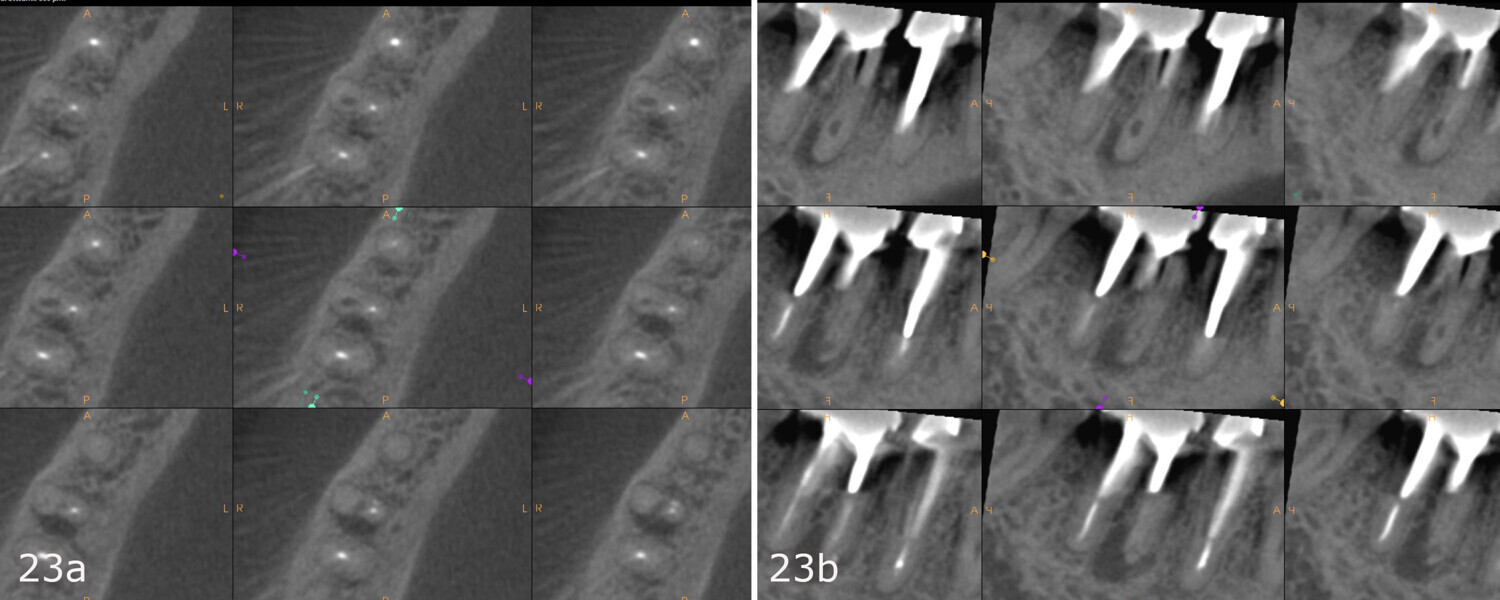

The patient was referred to Dr Karaś’s office for non-surgical root canal retreatment of tooth #46. The tooth was symptomatic, and the radiographic examination revealed a periapical lesion around the mesial root. The periapical lesion was clearly visible, but the shape of the root canal was not clear (Fig. 22). The examination was extended by CBCT imaging. The CBCT scan revealed internal resorption in the mesiobuccal canal and an isthmus and apical inflammatory root resorption in the apical area of the mesial root (Fig. 23). A cast post and prosthetic crown were also noted.